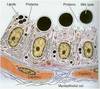

Different Stages of Follicle/Oocyte

FSH Indep

Primordial Follicles (non growing)

Primary/prenatral follicles (growing)

FSH dep

Secondary/antral follicles (growing)

Mature or Graafian follicles (preovulatory) (growing)

Ea follicle contains primary oocyte surrounded by 1 or multilayer follicular or granulosa cells

Primordial Follicle

Smallest & most numerous type of follicles in cortex of ovary.

Ea is composed of 1 layer of flat follicular cells around primary oocyte separated from stroma by basement mem

Primary oocyte arrested in prophase I - 1 nucleus, Golgi, RER, mitoch, lysosomes

Primary Follicles

Oocyte grows

- unilaminar primary follicle- primary surrounded by simple cuboidal or columnar follicular cells single layer

- multilaminar primary follicle- follicular cells prolif & stratify, & now are granulosa cells. Prolif of follicular cells is due to activin produced by primary oocyte

Secondary/Antral Follicles

Characterized by accumulations of fluid known as liquor folliculi among granulosa cells

Mature Graafian Follicle

Droplets of liquor folliculi coalesce to form single fluid filled chamber called antrum.

Granulosa cells rearrange & primary oocyte is surrounded by small group of granulosa cells called cumulus oophorus

Single layer of granulosa cells that immediately surrounds primary oocyte is called corona radiata